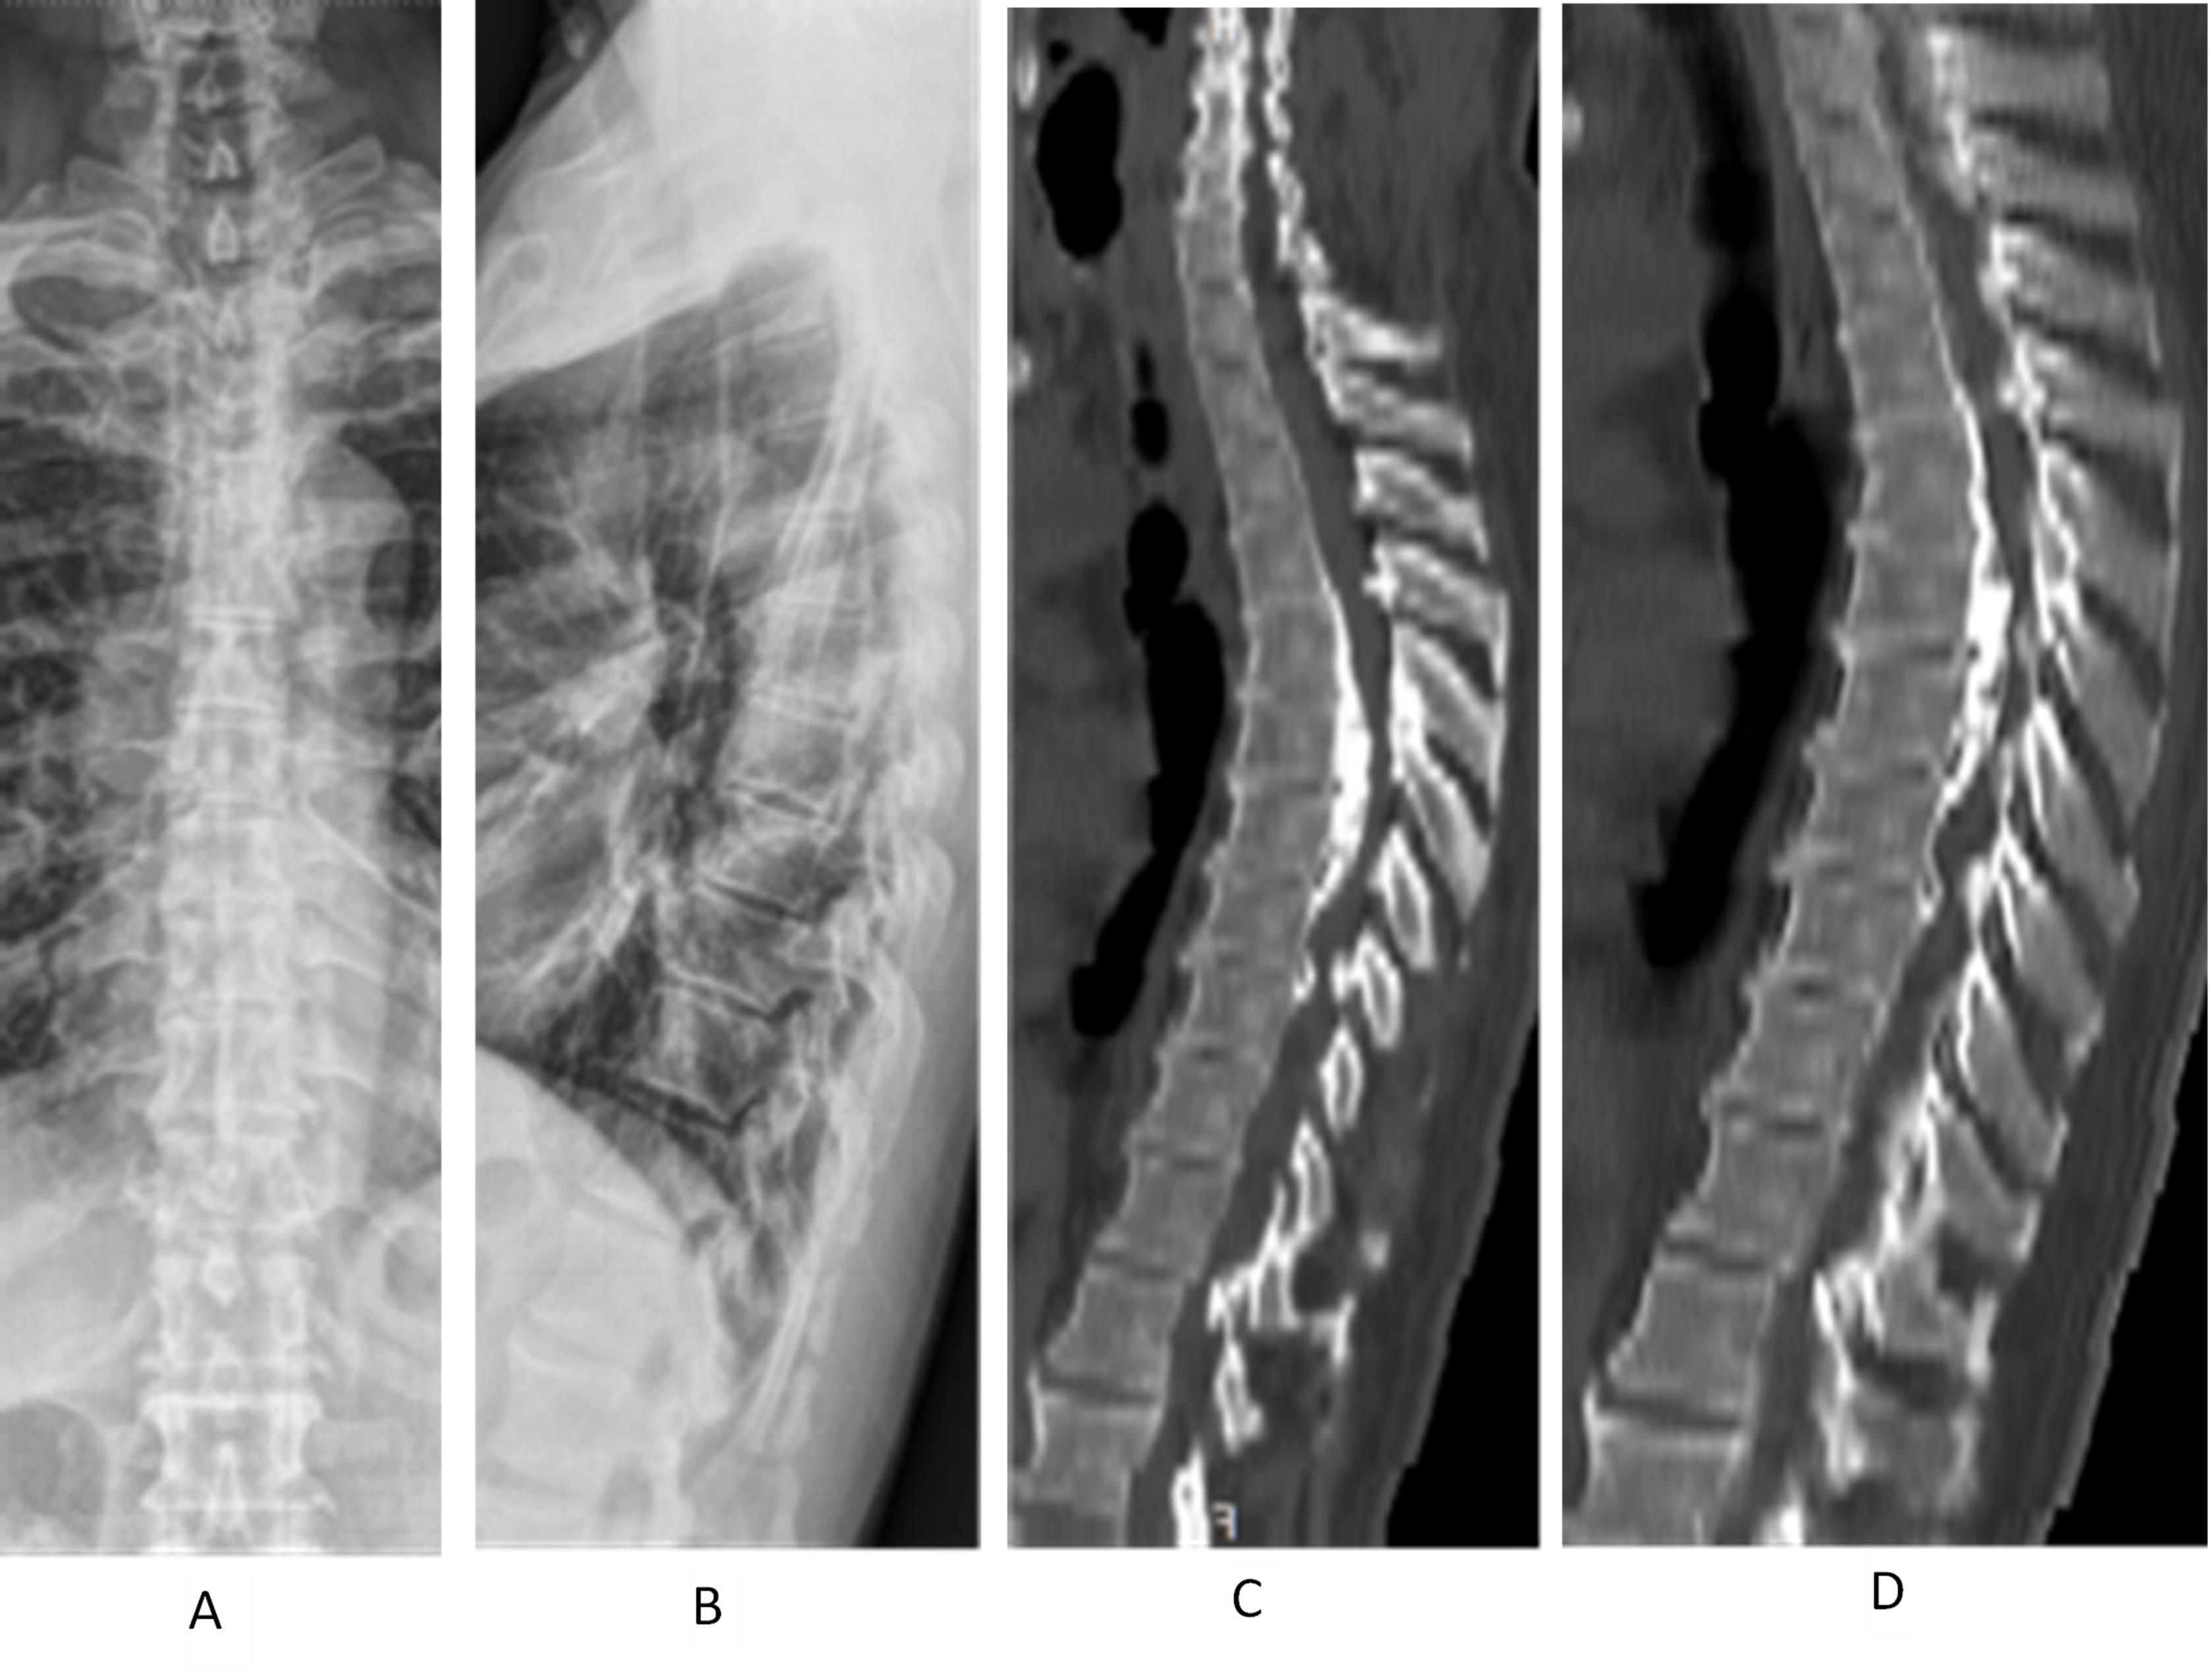

Figure 3 (A–D). Demonstrates a case of a male, 57 years old, thoracic posterior longitudinal ligament (PLL) ossification (continuous type), laminectomy, PLL ossification block cutting with ultrasonic bone knife system, and de-posteriorization orthopedic internal fixation. A and B show the frontal and lateral view of preoperative thoracic spine X-ray; C and D show the preoperative thoracic spine CT sagittal radiograph. T4–7 have continuous PLL ossification, protruding into the spinal canal. The stenosis segment has 37° of Cobb angle with posterior convexity.

Figure 3 (E–H). E shows the preoperative thoracic MRI: Ossification of the posterior longitudinal ligament (PLL) of T5–7 and ossification of the ligamentum flavum of T4–7 can be seen together with anterior and posterior compression of the segmental spinal cord. F and G show the postoperative thoracic X-ray: T3–8 pedicle pins were well positioned; H shows the postoperative thoracic CT sagittal view: T4–7 laminectomy was performed, and T5–6 PLL ossification was cut off to de-convex the kyphosis. Both facet joints were partially removed. The preoperative and postoperative Cobb's angles were 30° and 15°, respectively.